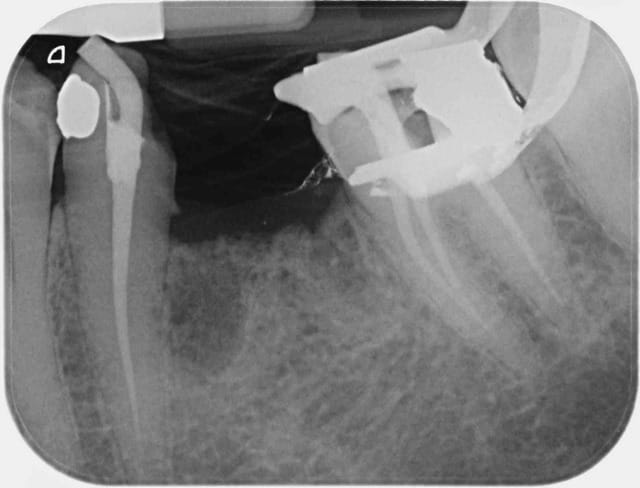

Ma première séance de ce matin concernait le secteur 2 d'un patient douillet : 1 anesthésie en un seul point, totalement indolore(acte qui dure certes 3 minutes), m'a permis de soigner 25, 26 et 27 parfaitement silencieuses, pulpes ET TISSUS MOUS compris (utile pour la pose de matrices, de coins interdentaires, de la digue...).

En partant, le patient repart travailler sans engourdissement.

Quand à la durée de l'anesthésie, je n'ai jamais été embêté, et une endo molaire dure plus souvent 60 minutes que 40. Pour ce patient, une seule anesthésie entre 35 et 37 m'a laissé tranquille pendant 1h20 sur les deux dents.

C1 mo8wyf - Eugenol

C3 kmhffi - Eugenol